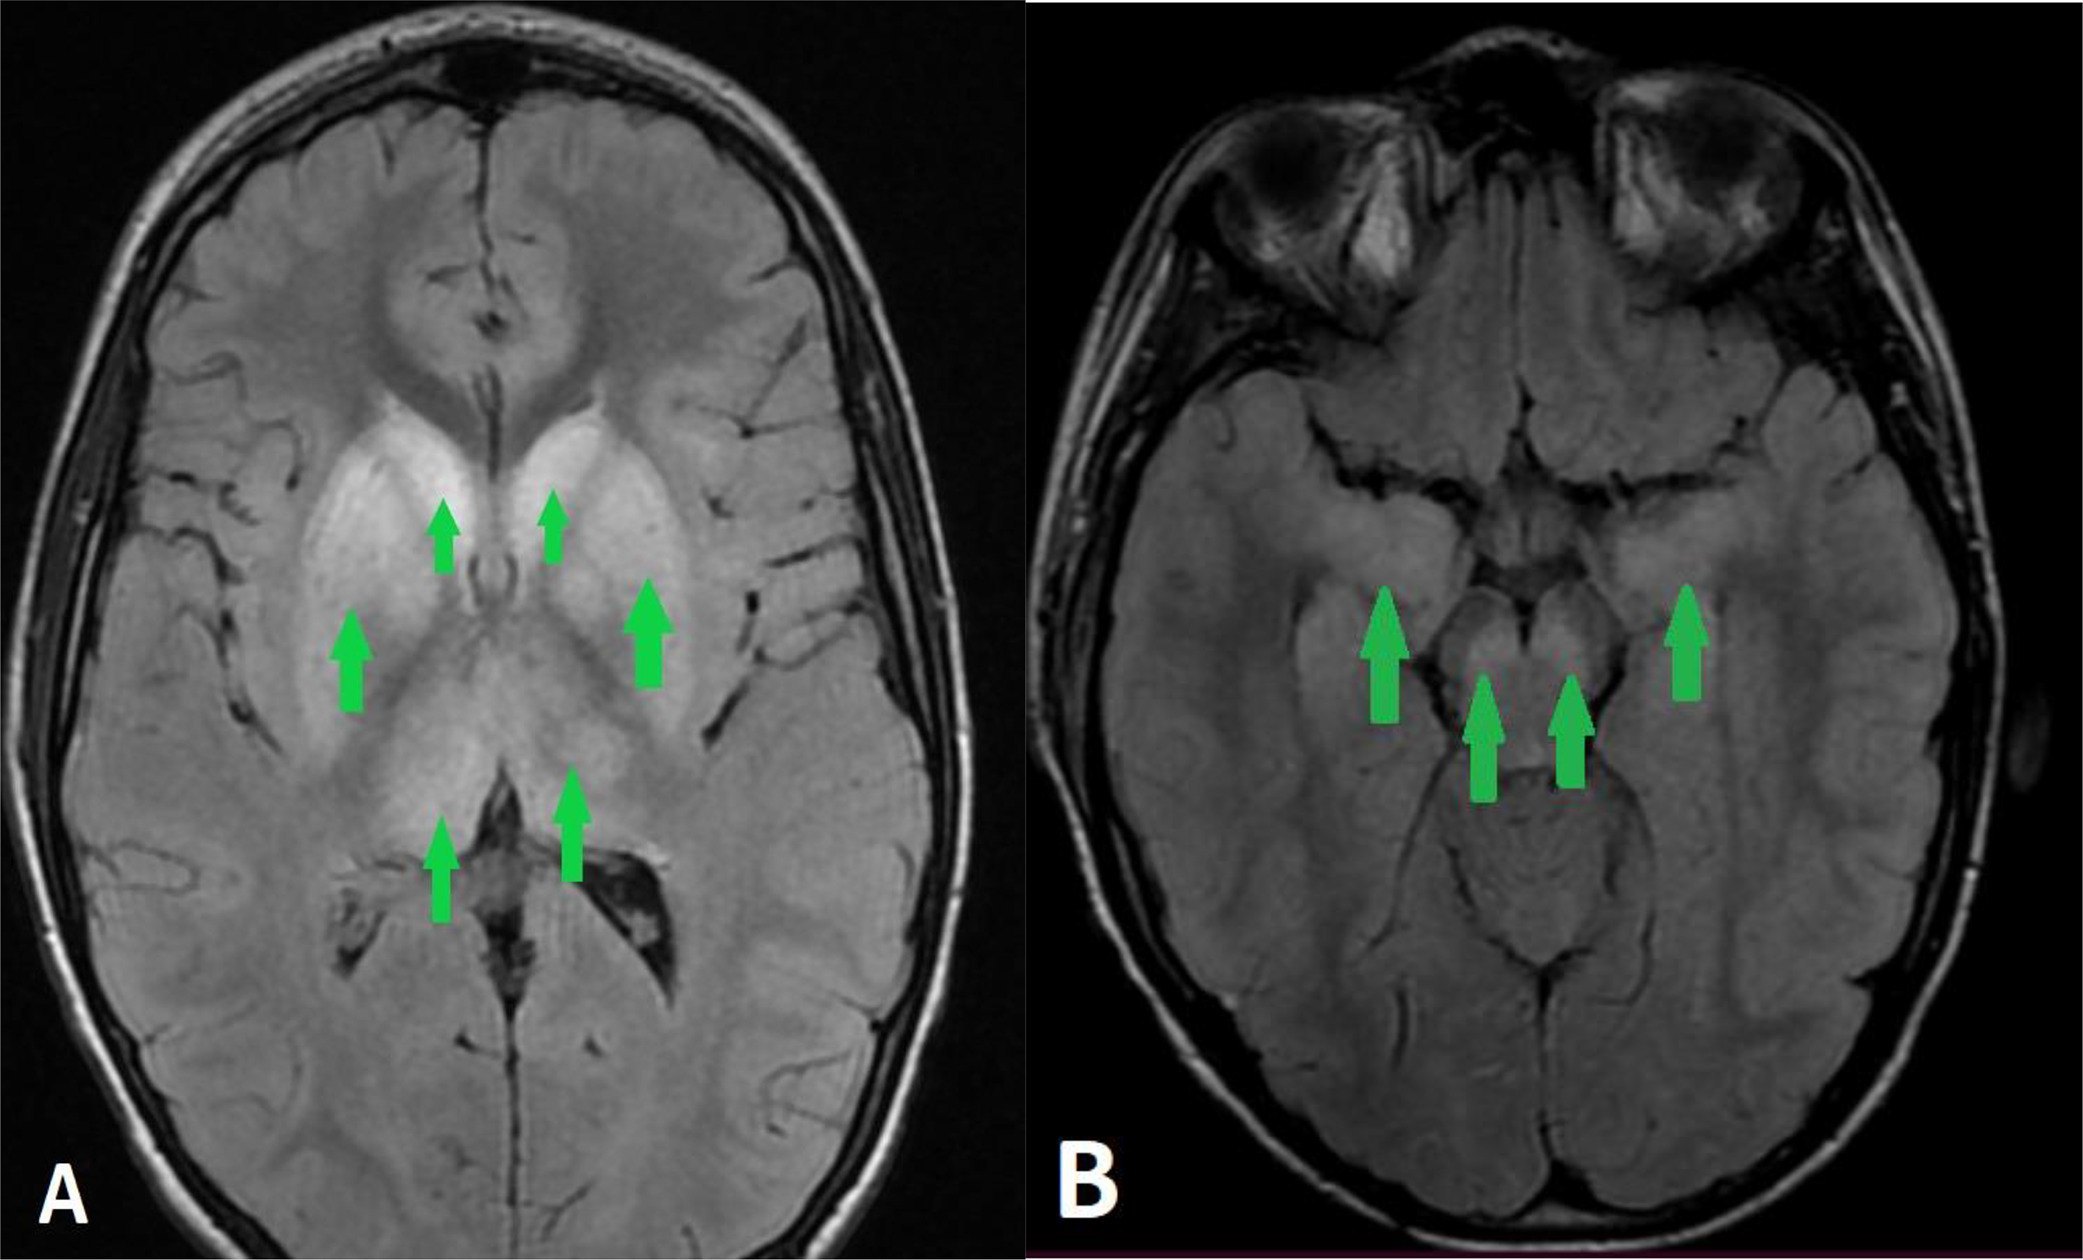

Важливо: підтвердити сказ можна лише тоді, коли його запідозрили. Діагностика передбачає спеціальне дослідження мозку людини або вже померлої тварини з використанням особливого фарбування, яке дозволяє виявити специфічні ураження нервових клітин. Якщо цього не зробити, лікар бачить лише загальну картину, запалення мозку або його оболонок, і встановлює діагноз енцефаліту чи менінгіту.